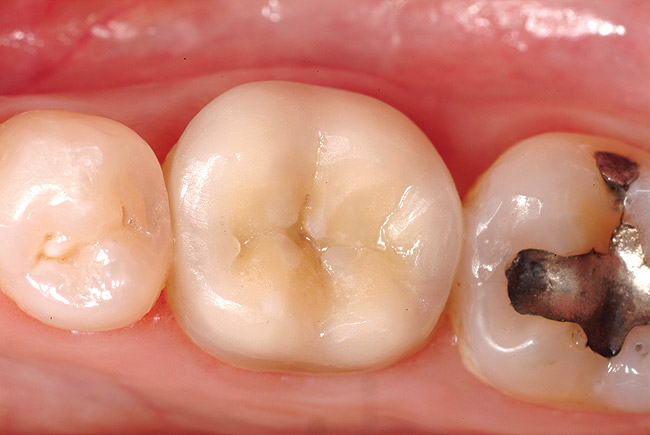

Figure 1a  A patient presents with large direct composite restorations and multiple crack lines in teeth Nos. 18 and 19. Tooth No. 19 was symptomatic to biting pressure.

Figure 1a

Figure 1b  The teeth were prepared for adhesively retained restorations. Note the significant ring of remaining enamel.

Figure 1b

Figure 1c  The final restorations restore and protect the compromised cusps.

Figure 1c

While in vitro studies do not definitively demonstrate a correlation between fracture resistance and cuspal coverage, cuspal coverage is still considered important in instances where the remaining tooth structure is less than one third to one half of the intercuspal distance.22,23 Other factors that support cuspal coverage of posterior teeth are the position of the tooth within the arch, with molars subject to greater bite forces and, therefore, exhibiting a greater need for cuspal coverage.24,25 Cracked teeth also warrant cuspal coverage (Figure 1A through Figure 1C).26,27